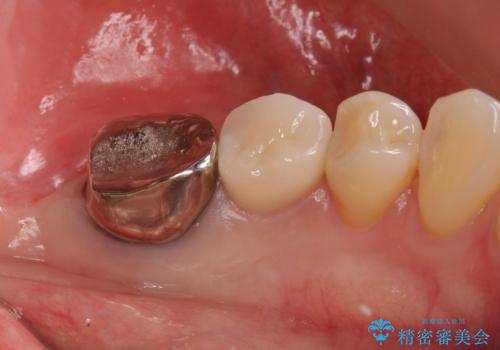

- 銀歯のやりかえ希望の患者様です。

症状もなく、レントゲンでも根尖病巣が見られないため

患者様と話し合った結果、中の土台は外さず、被せ物のみのやりかえとなりました。

レントゲン上で根尖病巣が見られた場合

中の土台を外して根管治療を行わなくてはなりません。